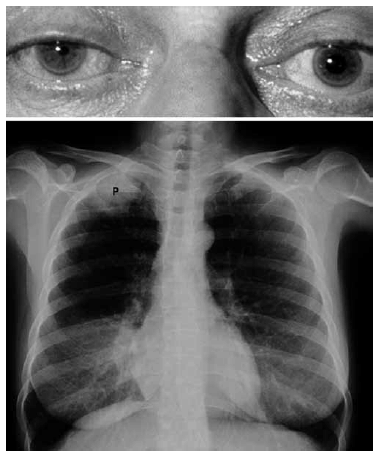

Mulher de 71 anos, tabagista (50 anos/maço), apresenta tosse produtiva, dor torácica à direita e em membro superior direito de caráter neuropático há um mês. Realizado RX tórax (imagem da fáscies da paciente e RX a seguir).

Diante do exposto, é correto dizer que a paciente apresenta